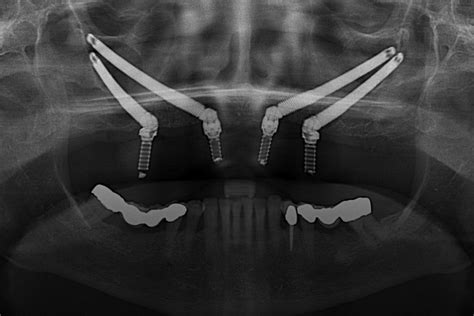

4. Implantes Cigomáticos

En cambio, si te faltan todos o la mayoría de los dientes y tienes mucha atrofia ósea, los implantes que se sostienen en otros huesos pueden ser una opción para ti. Los implantes cigomáticos son aditamentos largos que se colocan en otros sitios más alejados de tu boca para brindar el soporte que necesitamos para rehabilitar tu dentadura.

Estos implantes se colocan en tu hueso cigomático o, lo que es lo mismo, en tus pómulos. Son otro tipo de implantes especiales, de mayor longitud que los convencionales. Estas zonas de hueso son muy compactas, lo que genera una elevada tasa de éxito.

Implantes Cigomáticos: Una solución para la atrofia ósea severa.